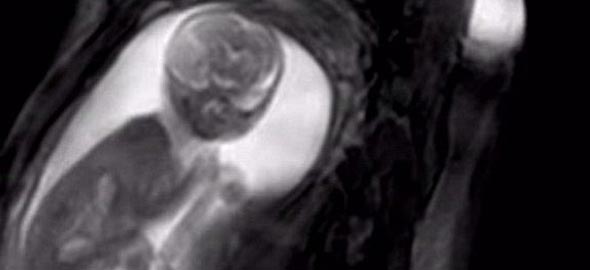

Για τις ανάγκες της μελέτης, προβλήθηκαν εικόνες με φως μέσω του τοιχώματος της μήτρας, σε δεκάδες εγκύους. Στη συνέχεια παρακολουθήθηκαν οι αντιδράσεις εμβρύων 34 εβδομάδων, μέσω υπερήχου 4-D.

Τα έμβρυα έδειξαν να στρέφουν το κεφάλι τους, για να κοιτάξουν τις εικόνες με σχήμα προσώπου, περισσότερο από οποιαδήποτε άλλη εικόνα. Τα αποτελέσματα της έρευνας δημοσιεύτηκαν στις 8 Ιουνίου, στο επιστημονικό περιοδικό Current Biology.